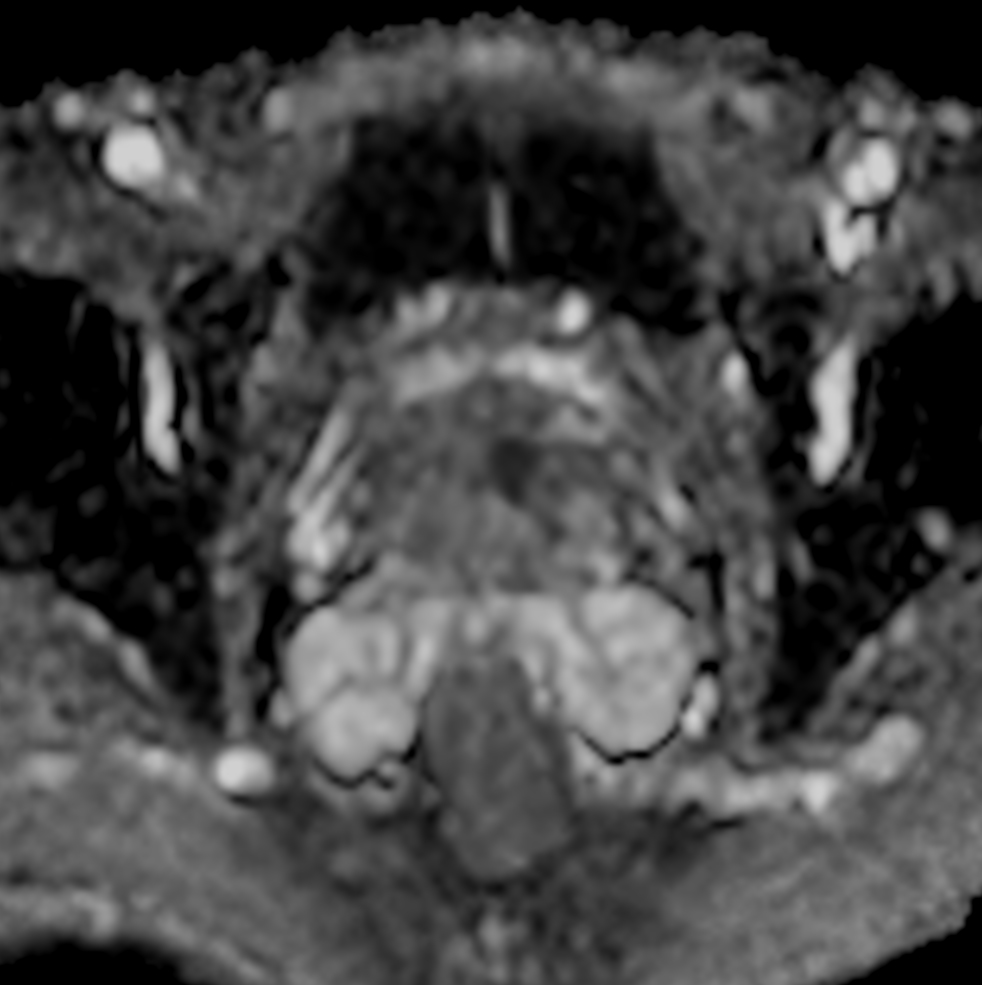

Axial DWI (b1000, ADC)